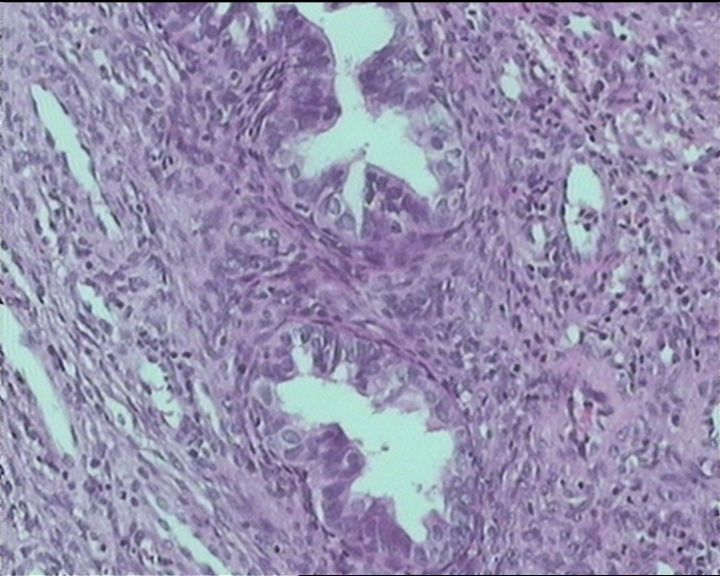

54岁女性,临床“宫颈息肉”送检;巨检:组织一块1。5*1CM,灰红。

输卵管粘膜化生

细胞及腺体均有异形,图6、11、16象有纤维间质反应,考虑高级别上皮内瘤变/原位癌,腺癌不能除外。

Sternberg病理学上诊断宫颈原位腺癌的标准是腺体的上皮去粘液分化,呈乳头状或筛网状增生,核分裂易见,这例显然达不到此标准。此例还是归入到腺上皮不典型增生为好。

It is benign. Benign endocervical polyp with tubal metaplasia.

杨老师说它是良性的,是个颈管内膜息肉伴输卵管上皮化生,良性